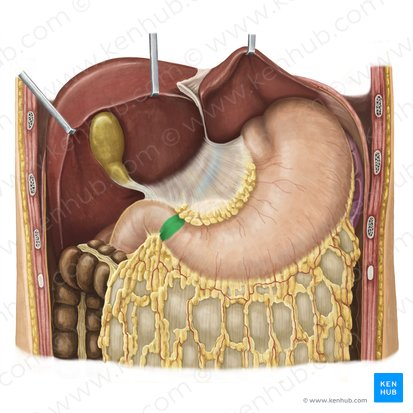

Liver

a large organ located in the upper right abdomen that produces bile, detoxifies blood, and performs many other metabolic functions.

Considered as the largest gland in the body

Stomach

a J-shaped organ located in the upper abdomen that stores, mixes, and digests food.

Spleen

An organ located in the upper left abdomen that is part of the lymphatic system, filtering blood and storing white blood cells

Gallbladder

A small, pear-shaped organ located beneath the liver that stores and concentrates bile produced by the liver.